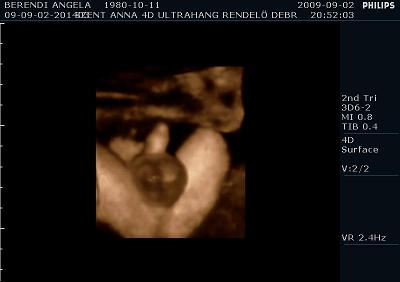

Ma voltunk UH-on. És a méretei alapján még mindig egy héttel idősebbnek nézik, de súlya tök normális 2350 gramm. Szóval azt mondják nem lesz akkora mint a kis Levi manó volt. Ennek azért örülök mert nagyobb az esély hogy meg tudom szülni, mivel nekem az első császár volt. Szóval drukkoljatok lányok!!